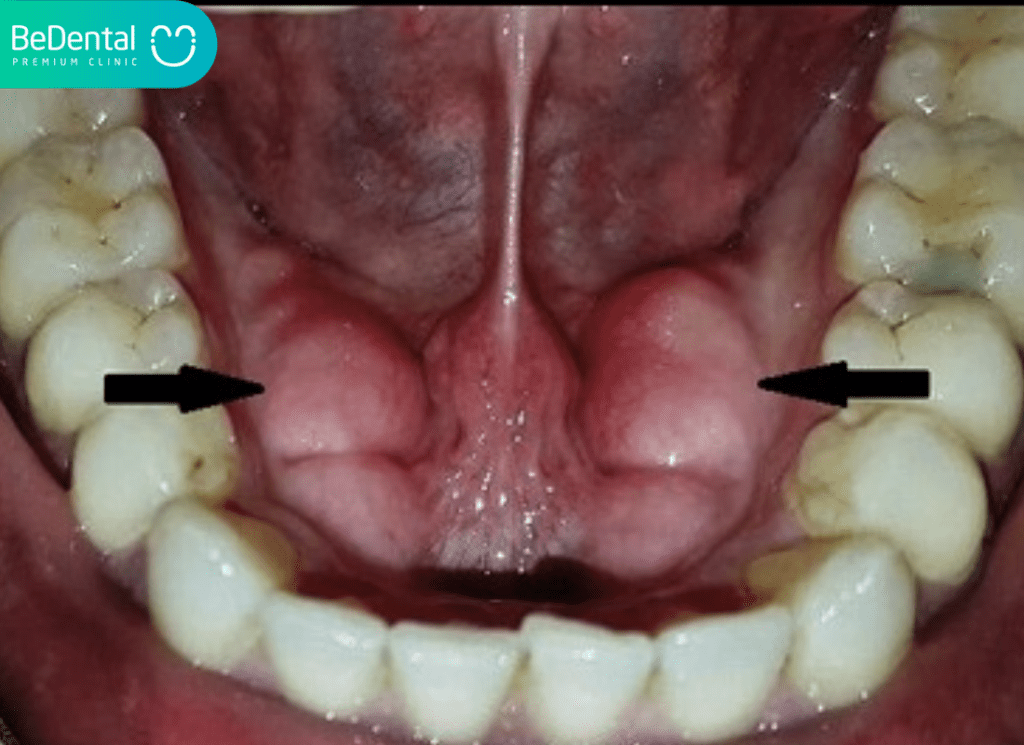

U lồi hàm (Osteoma):

U lồi hàm là một dạng u xương lành tính, phát triển chậm và thường không gây đau. Khối u này thường xuất hiện ở xương hàm trên hoặc hàm dưới.Khi xuất hiện trong khoang miệng, khối u có thể tạo thành một cục cứng dưới niêm mạc mà nổi cục trong miệng không đau.

Tình trạng này không nguy hiểm và không cần can thiệp trừ khi kích thước khối u lớn, ảnh hưởng đến chức năng nhai hoặc gây mất thẩm mỹ.